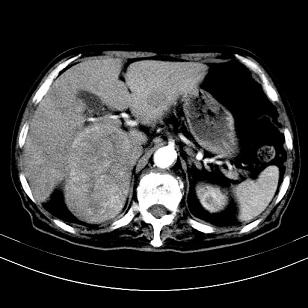

标题: CT19407:肝内还是肝外原发性肿瘤??

男,63岁,高血压病史40余年,

来源-右侧肾上腺。

考虑右侧肾上腺巨大占位;恶性?

肝内多发低密度找;转移瘤?

另:右肾结识,多发小囊肿。

考虑右肝后叶肝癌伴多发肝内转移

考虑右肝后叶肝癌(部分外生)伴肝内多发性转移;右侧肾上腺区恶性肿瘤并肝转移待排。

考虑右侧肾上腺肿瘤并肝内多发转移。右侧肾上腺呈“八”字形,包括内侧枝及外侧枝,内侧枝受压,考虑外侧枝原发肿瘤。”